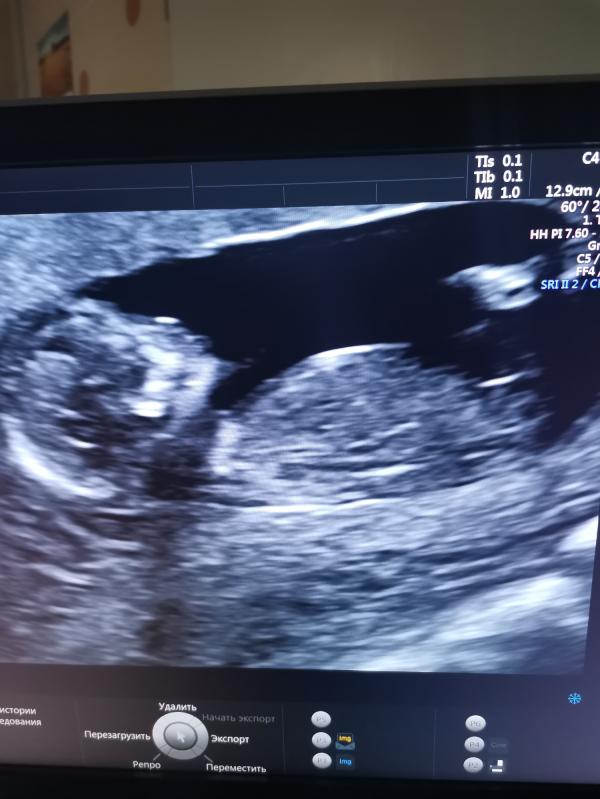

Оставлю это здесь на память 😀Наш первый скрининг, срок 12+6. Очень переживала по поводу этого дня. На УЗИ сказали всё хорошо, скорее всего девочка. Во время УЗИ подпрыгивает в животике, так радостно было на душе, мне кажется у меня улыбка до ушей была🤗